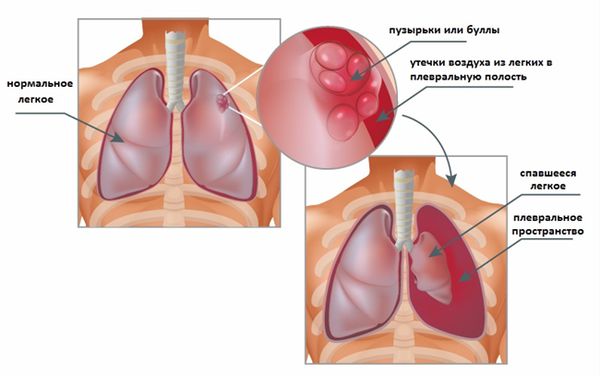

Анатомия межплеврального пространства